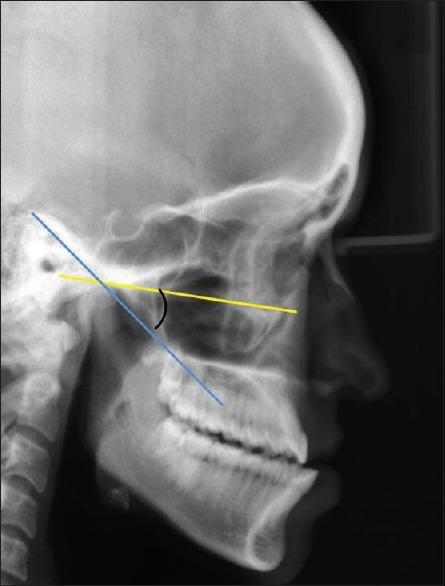

One-hundred twenty dentulous subjects between age group of 20-40 years, free of signs and symptoms of any temporomandibular diseases were selected. The sagittal condylar guidance was determined by protrusive interocclusal records and transferred to a semi-adjustable articulator through a face bow. The condylar guidance angles obtained were tabulated. The sagittal outline of the articular eminence and glenoid fossa were traced on panoramic and lateral cephalogram radiographs. The sagittal condylar path inclination was constructed. This was related to the Frankfurt's horizontal plane on radiograph to determine the radiographic angle of sagittal condylar guidance. The comparison of protrusive interocclusal records was done with the angles obtained by panoramic and lateral cephalogram radiograph tracings.

选取120名年龄在20至40岁之间、无任何颞下颌疾病体征和症状的无牙颌受试者。通过前伸牙合记录确定髁突矢状向引导,并通过面弓转移至半可调式牙合架。将获得的髁突引导角制成表格。在全景片和头颅侧位片上描绘关节结节和关节窝的矢状轮廓。构建髁突矢状向路径倾斜度。将其与X线片上的法兰克福水平面相关联,以确定髁突矢状向引导的X线角度。将前伸牙合记录与通过全景片和头颅侧位片描记获得的角度进行比较。